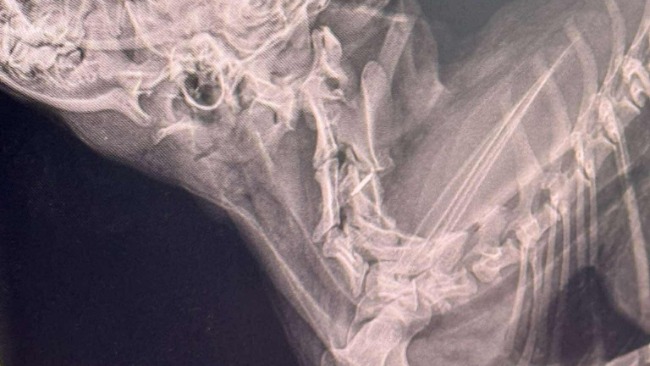

Dostaliśmy wyniki tomografu naszej podopiecznej Wiktorii… i niestety – nie są dobre.

Diagnoza: niestabilność szczytowo-obrotowa z podwichnięciem obrotnika C2, co powoduje ucisk na rdzeń kręgowy. To właśnie dlatego Wiktoria nie potrafi normalnie chodzić. Każdy krok to ogromny wysiłek i zagrożenie – może dojść do pogłębienia urazu, a w najgorszym przypadku – do trwałego paraliżu.

Dalsza poprawa jest niemożliwa bez neurochirurgicznej interwencji.Lekarze stwierdzili niedowład kończyn piersiowych, bardziej nasilony po prawej stronie – wszystko wskazuje na ucisk w odcinku szyjnym rdzenia kręgowego.